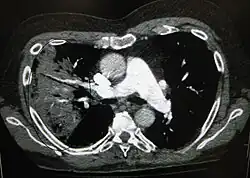

Obrazy RTG zapalenia płuc można sklasyfikować jako przedstawiające płatowe zapalenie płuc, oskrzelowe zapalenie płuc (znane również jako zrazikowe zapalenie płuc) oraz śródmiąższowe zapalenie płuc[40]. Bakteryjne, pozaszpitalne zapalenie płuc w postaci klasycznej wykazuje konsolidację jednego segmentarnego płata płuca i znane jest jako płatowe zapalenie płuc[20]. Wyniki mogą jednak się różnić, a w innych typach zapalenia płuc powszechne są inne wzory zmian[20]. W aspiracyjnym zapaleniu płuc obraz może wykazywać dwustronną nieprzezroczystość głównie u podstawy płuc i po prawej stronie[20]. Obrazy wirusowego zapalenia płuc mogą wydawać się normalne, płuca nadmiernie rozdęte, z dwustronnymi niejednolitymi obszarami lub podobne do bakteryjnego zapalenia płuc z konsolidacją płata[20]. Zmiany mogą nie być widoczne w obrazach RTG we wczesnych stadiach choroby, zwłaszcza w wypadku odwodnienia; mogą być również trudne do zinterpretowania u osób otyłych lub z historią chorób płuc[11]. W ostatnich latach istotne badania kliniczne wykazały, że ultrasonografia klatki piersiowej, wykonywana przez doświadczonych specjalistów, charakteryzuje się dokładnością diagnostyczną równą, a nawet przewyższającą radiografię klatki piersiowej w diagnostyce zapalenia płuc. Podejście to znajduje coraz szersze zastosowanie w praktyce klinicznej[41]. W trudnych do określenia przypadkach dodatkowe informacje można uzyskać dzięki tomografii komputerowej[20].

Rzadko bakterie w płucu tworzą kieszonkę zakażonego płynu zwaną ropniem płuca[74]. Ropnie płuca są zazwyczaj widoczne na prześwietleniu klatki piersiowej, jednak często trzeba wykonać tomografię komputerową klatki piersiowej dla potwierdzenia diagnozy[74]. Ropnie występują zazwyczaj w przypadku zapalenia płuc wskutek aspiracji i często zawierają kilka rodzajów bakterii. Leczenie ropnia polega najczęściej na długotrwałym przyjmowaniu antybiotyków, choć czasem wymaga zdrenowania przez chirurga bądź radiologa[74].